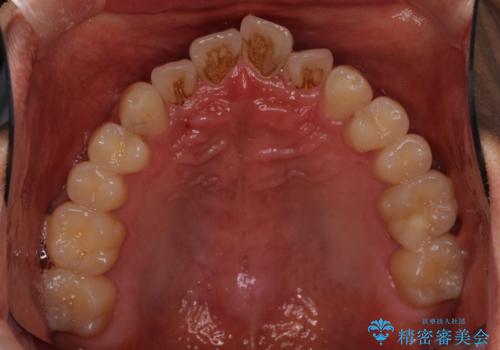

気になる前歯のデコボコをインビザラインで解消

- 前歯のデコボコを気にして来院された患者様です。

主に下顎歯列全体の後方移動とIPR(歯と歯の間を削る)によってデコボコが解消するように設計し、インビザラインにより治療を行うこととしました。

インビザライン矯正特有の、治療後半で前歯のみが強く接触する症状が発現し、咬み合わせ改善に期間を要することとなりました。